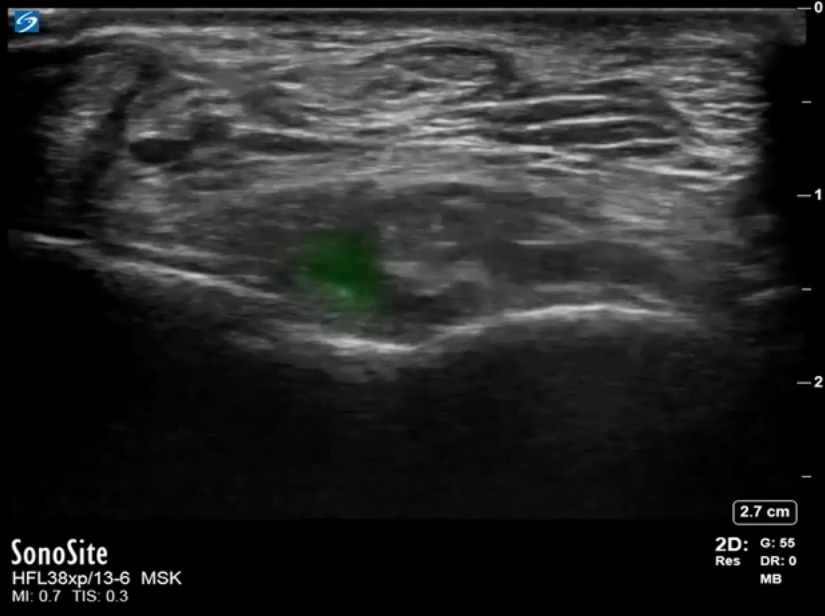

Foot & Ankle Anterior Recess Tibiotalar Joint Short Axis Image

Highlighted Area: Small Effusion in the Tibiotalar Joint